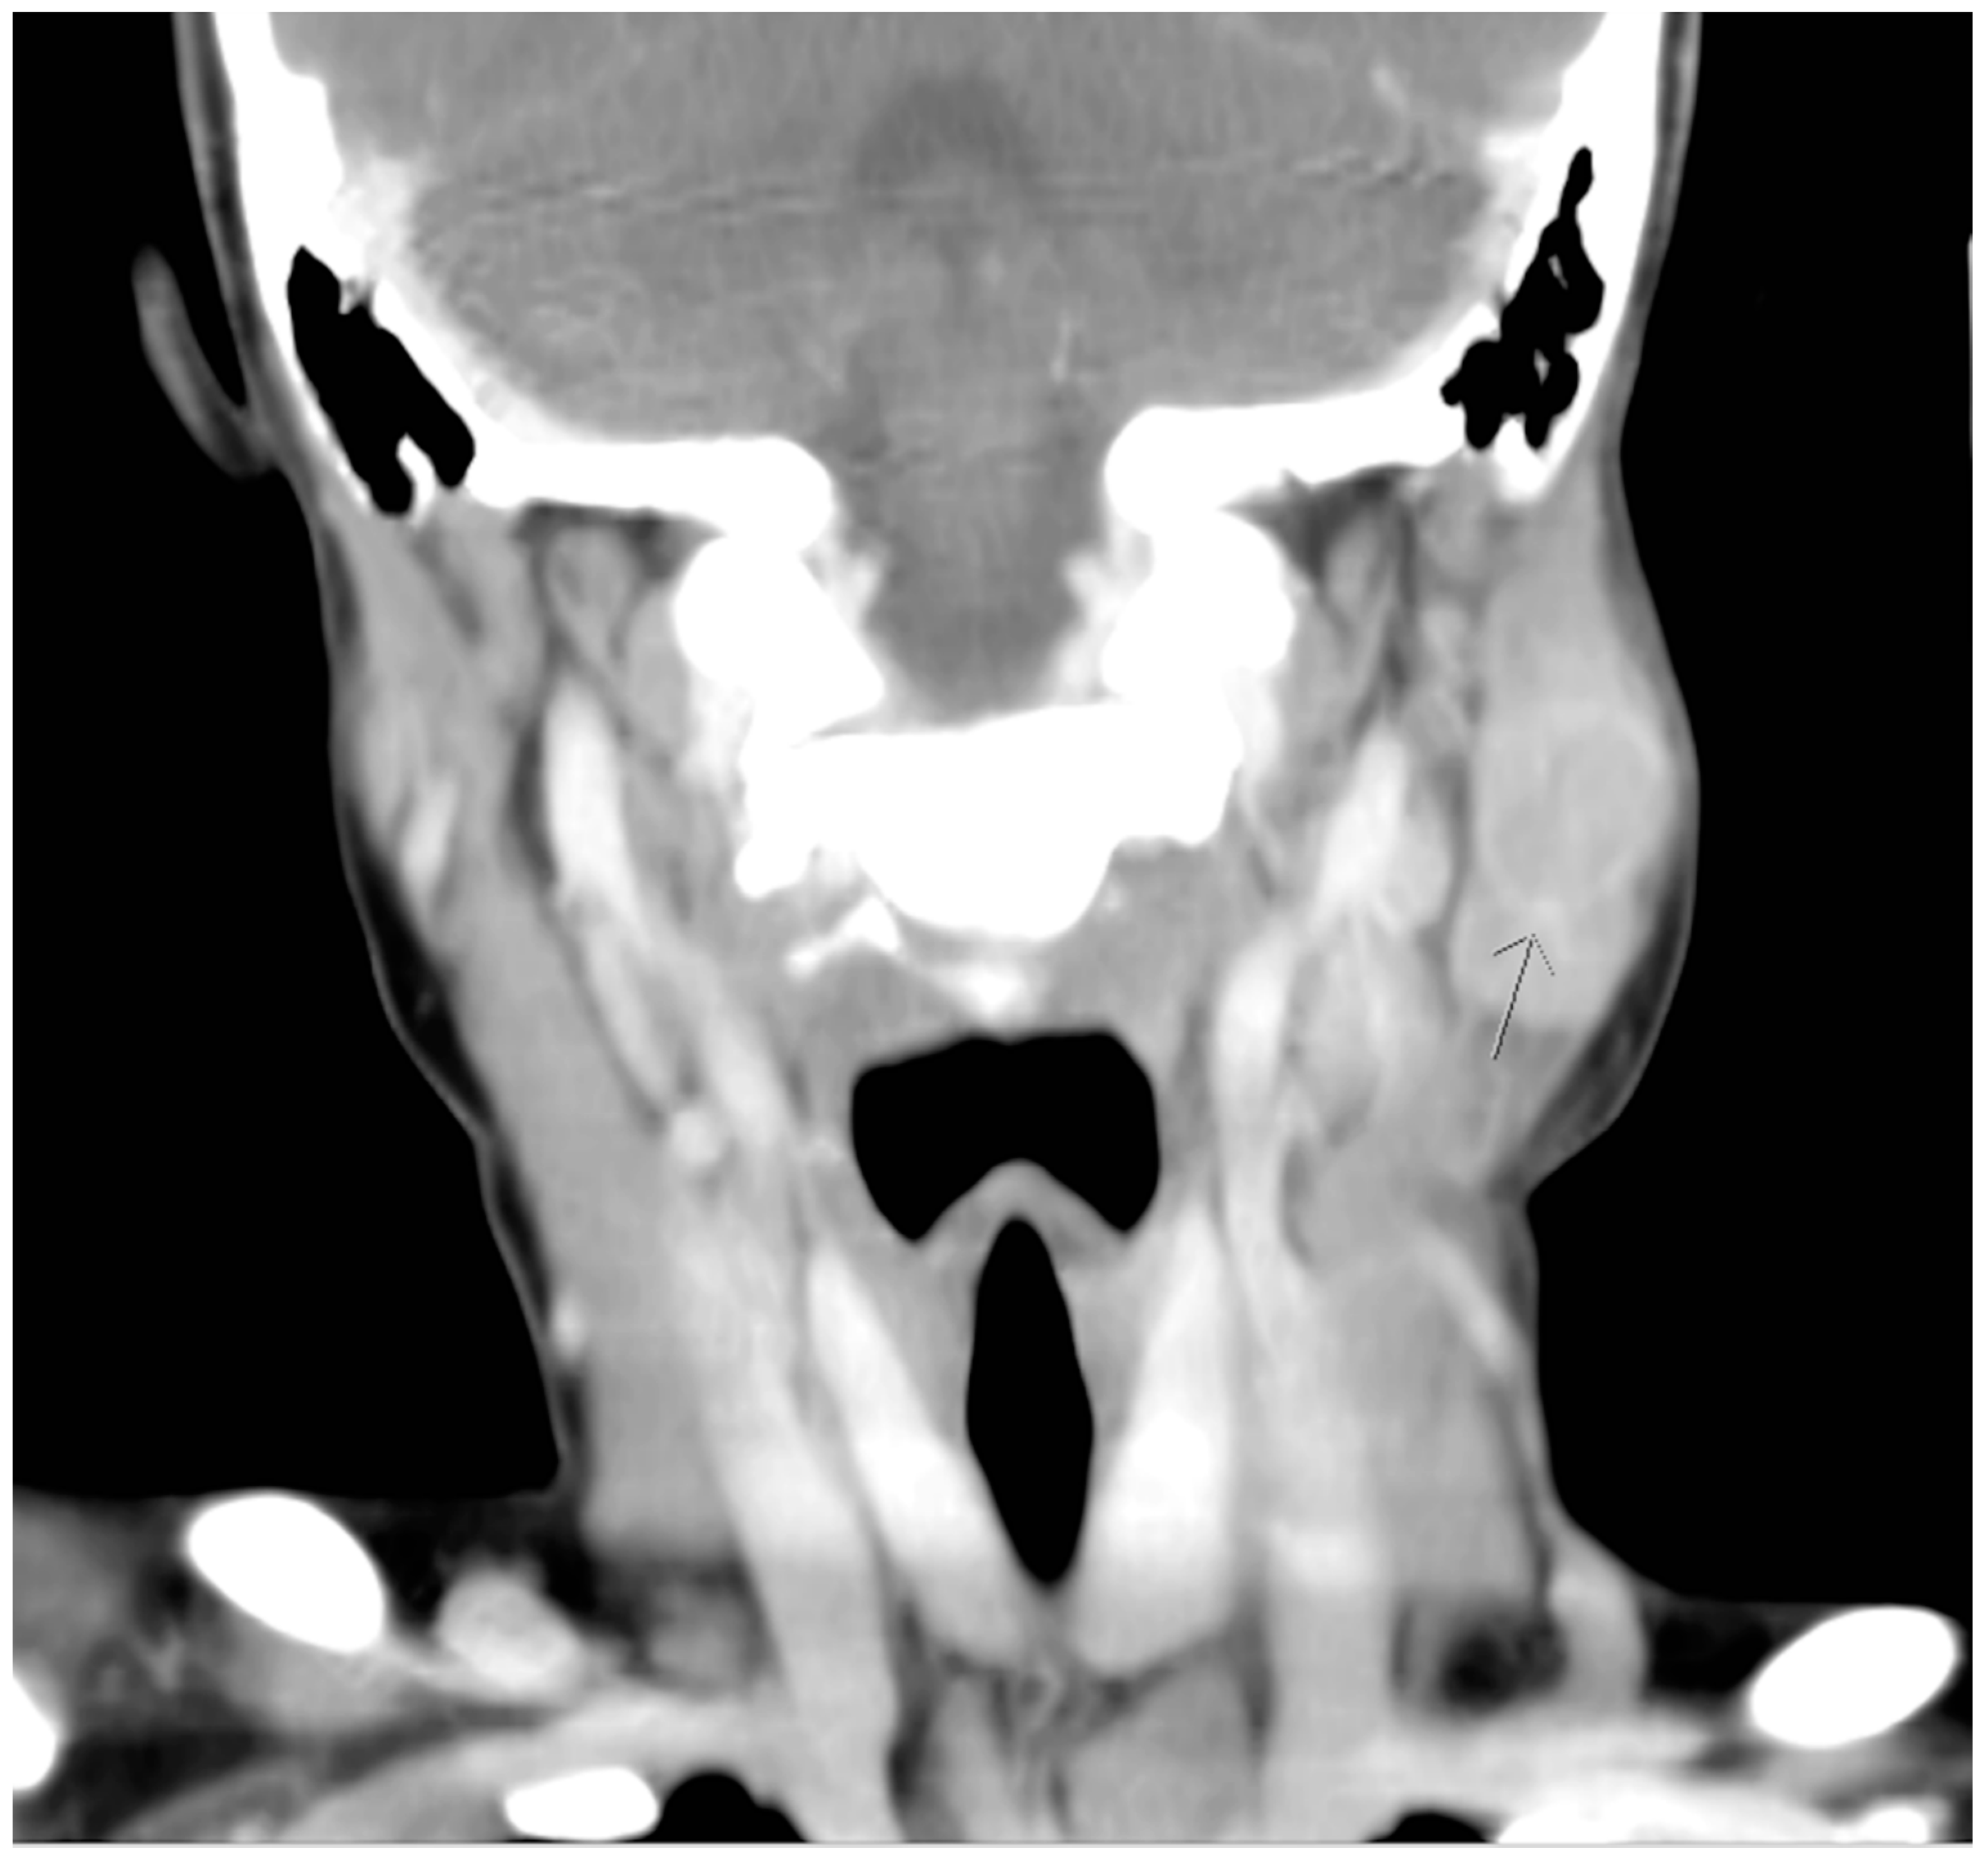

Although defervescence was observed on the seventh day after admission, the size of the mass was stationary. On the third day of hospitalization, azithromycin was prescribed based on the positive results of Mycoplasma pneumonia IgG and IgM serological tests. Nevertheless, the mass remained unchanged with prominent tenderness. Furthermore, a new round mass was observed on the ipsilateral part of the neck, which was located approximately 5 cm lower than the first mass; the size of this newly emerged mass was 2 × 2 cm2 and it was also hard, tender with well-defined margin. Computed tomographic (CT) scanning of the head and neck was therefore arranged, which revealed lymphadenopathy in the bilateral necks and a hypodense cyst with ill-defined margin in the left parotid gland. (Figure 2 and Figure 3). Based on the radiographic findings, a mumps virus immunoglobulin M (IgM) serology test was conducted.

Figure 2. Coronal computed tomographic view revealing a hypodense cyst with ill-defined margin in the left parotid gland. (arrow head).